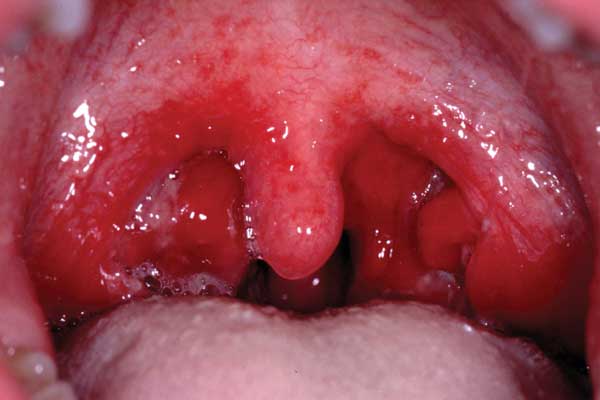

Group A streptococcus is the most common bacterial cause of acute pharyngitis accounting for approximately 5-10% of cases in adults.8, 9 Several studies have attempted to differentiate between group A streptococcal and viral causes based on the clinical features.

A systematic review has shown that the Centor scoring system (see box 1, below) may help categorise the patient's risk for group A streptococcal infection.10

Other organisms that may cause acute pharyngitis include:11

- Coxsackie virus A

- Epstein-Barr virus - infectious mononucleosis

- Cytomegalovirus

- Human immunodeficiency virus - as part of the primary infection

- Non-group A streptococci

- Corynebacterium diphtheriae - rare in the developed world

- Neisseria gonorrhoeae

- Arcanobacterium haemolyticum

- Mycoplasma pneumoniae - isolated from patients with symptomatic pharyngitis and controls, significance unclear

- Chlamydia pneumoniae - may occur as an isolated URTI or with pneumonia